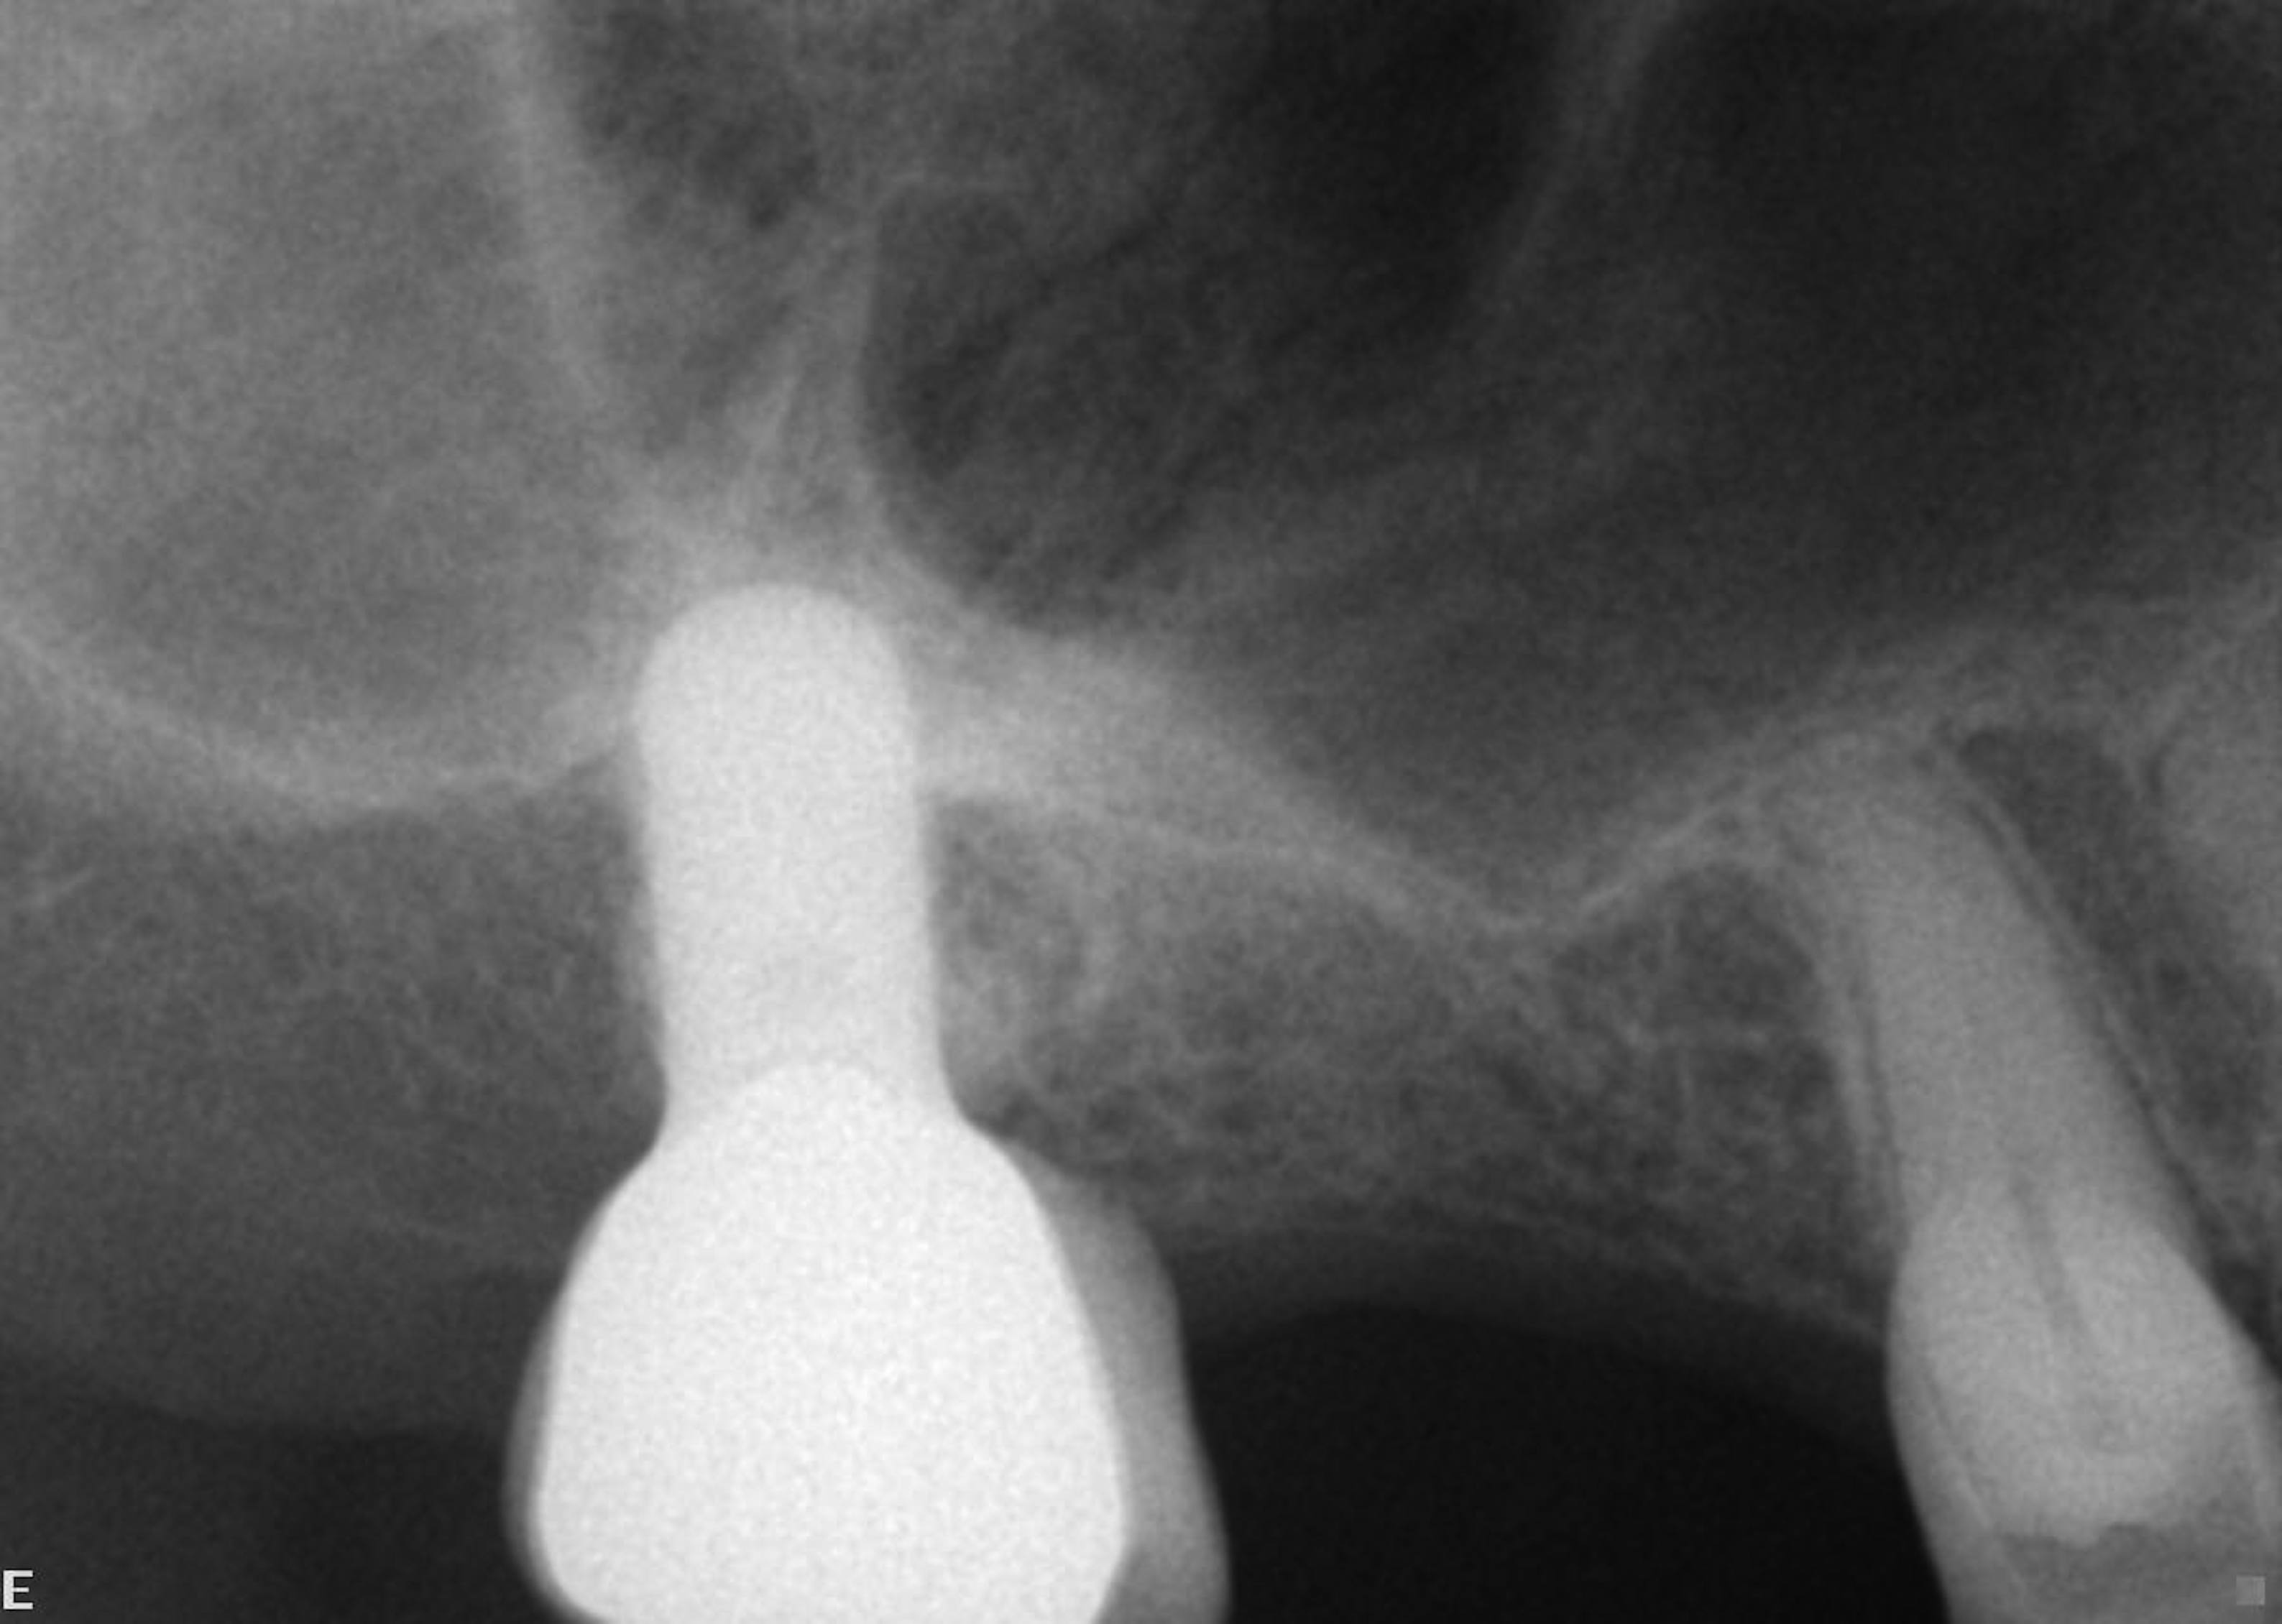

The pretreatment radiograph suggesting more than 2 mm of subantral alveolar bone.

Figure 21

Cross-sectional view of the edentulous site demonstrating minimal bone height below the sinus floor.

Figure 22

A patient who had received treatment 10 years ago for implants in the mandibular arch said her general dentist wanted to place an implant in site No. 3, using a hammer. Although that clinician believed the site had sufficient bone based on a periapical x-ray findings (Figure 21), the findings from a cross-sectional computed tomography scan helped determine that she had less than 3 mm of bone in the ridge (Figure 22). Froum et al14 and Tarnow et al15 both demonstrated the efficacy of combining rhBMP-2/ACS with mineralized bone allograft in sinus graft procedures. Marx et al16 demonstrated the combination of this growth factor with mineralized allograft and PRP to reconstruct severe maxillary defects. Given the 4 mm of minimal requirement for simultaneous implant placement, the author performed a lateral window sinus graft. An absorbable collagen sponge hydrated with rhBMP-2 was combined with mineralized bone allograft and used to obturate the site after reflection of the Schneiderian membrane along the medial sinus wall. A portion of the rhBMP-2/ACS was adapted over the grafted window osteotomy (Figure 23). After healing for approximately 5 months, the patient received a computer-guided implant surgery (Figure 24). The implant was restored with a screw-retained crown after a healing period of approximately 3 months.